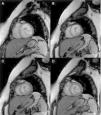

A 36-year-old woman was referred for medical evaluation prior to non-cardiac surgery. She was healthy and only complained of sporadic palpitations. The 12-lead electrocardiogram showed sinus rhythm and left bundle branch block. Transthoracic echocardiography revealed a normally functioning, slightly dilated left ventricle (LV), with the interventricular septum bulging toward the right ventricle (RV), which was elongated and wrapped around the LV (Figure 1; Supplementary material Videos S1 and S2). The papillary muscles were structurally abnormal and presented an apical origin, findings better visualized in contrast images (Figure 2; Videos S3–S5). Cardiac magnetic resonance confirmed the presence of a truncated LV, a complex network of papillary muscles of apical origin, and a banana-shaped, normally functioning RV (Figures 3 and 4; Videos S6–S8). There was no evidence of fatty infiltration or late enhancement with gadolinium.